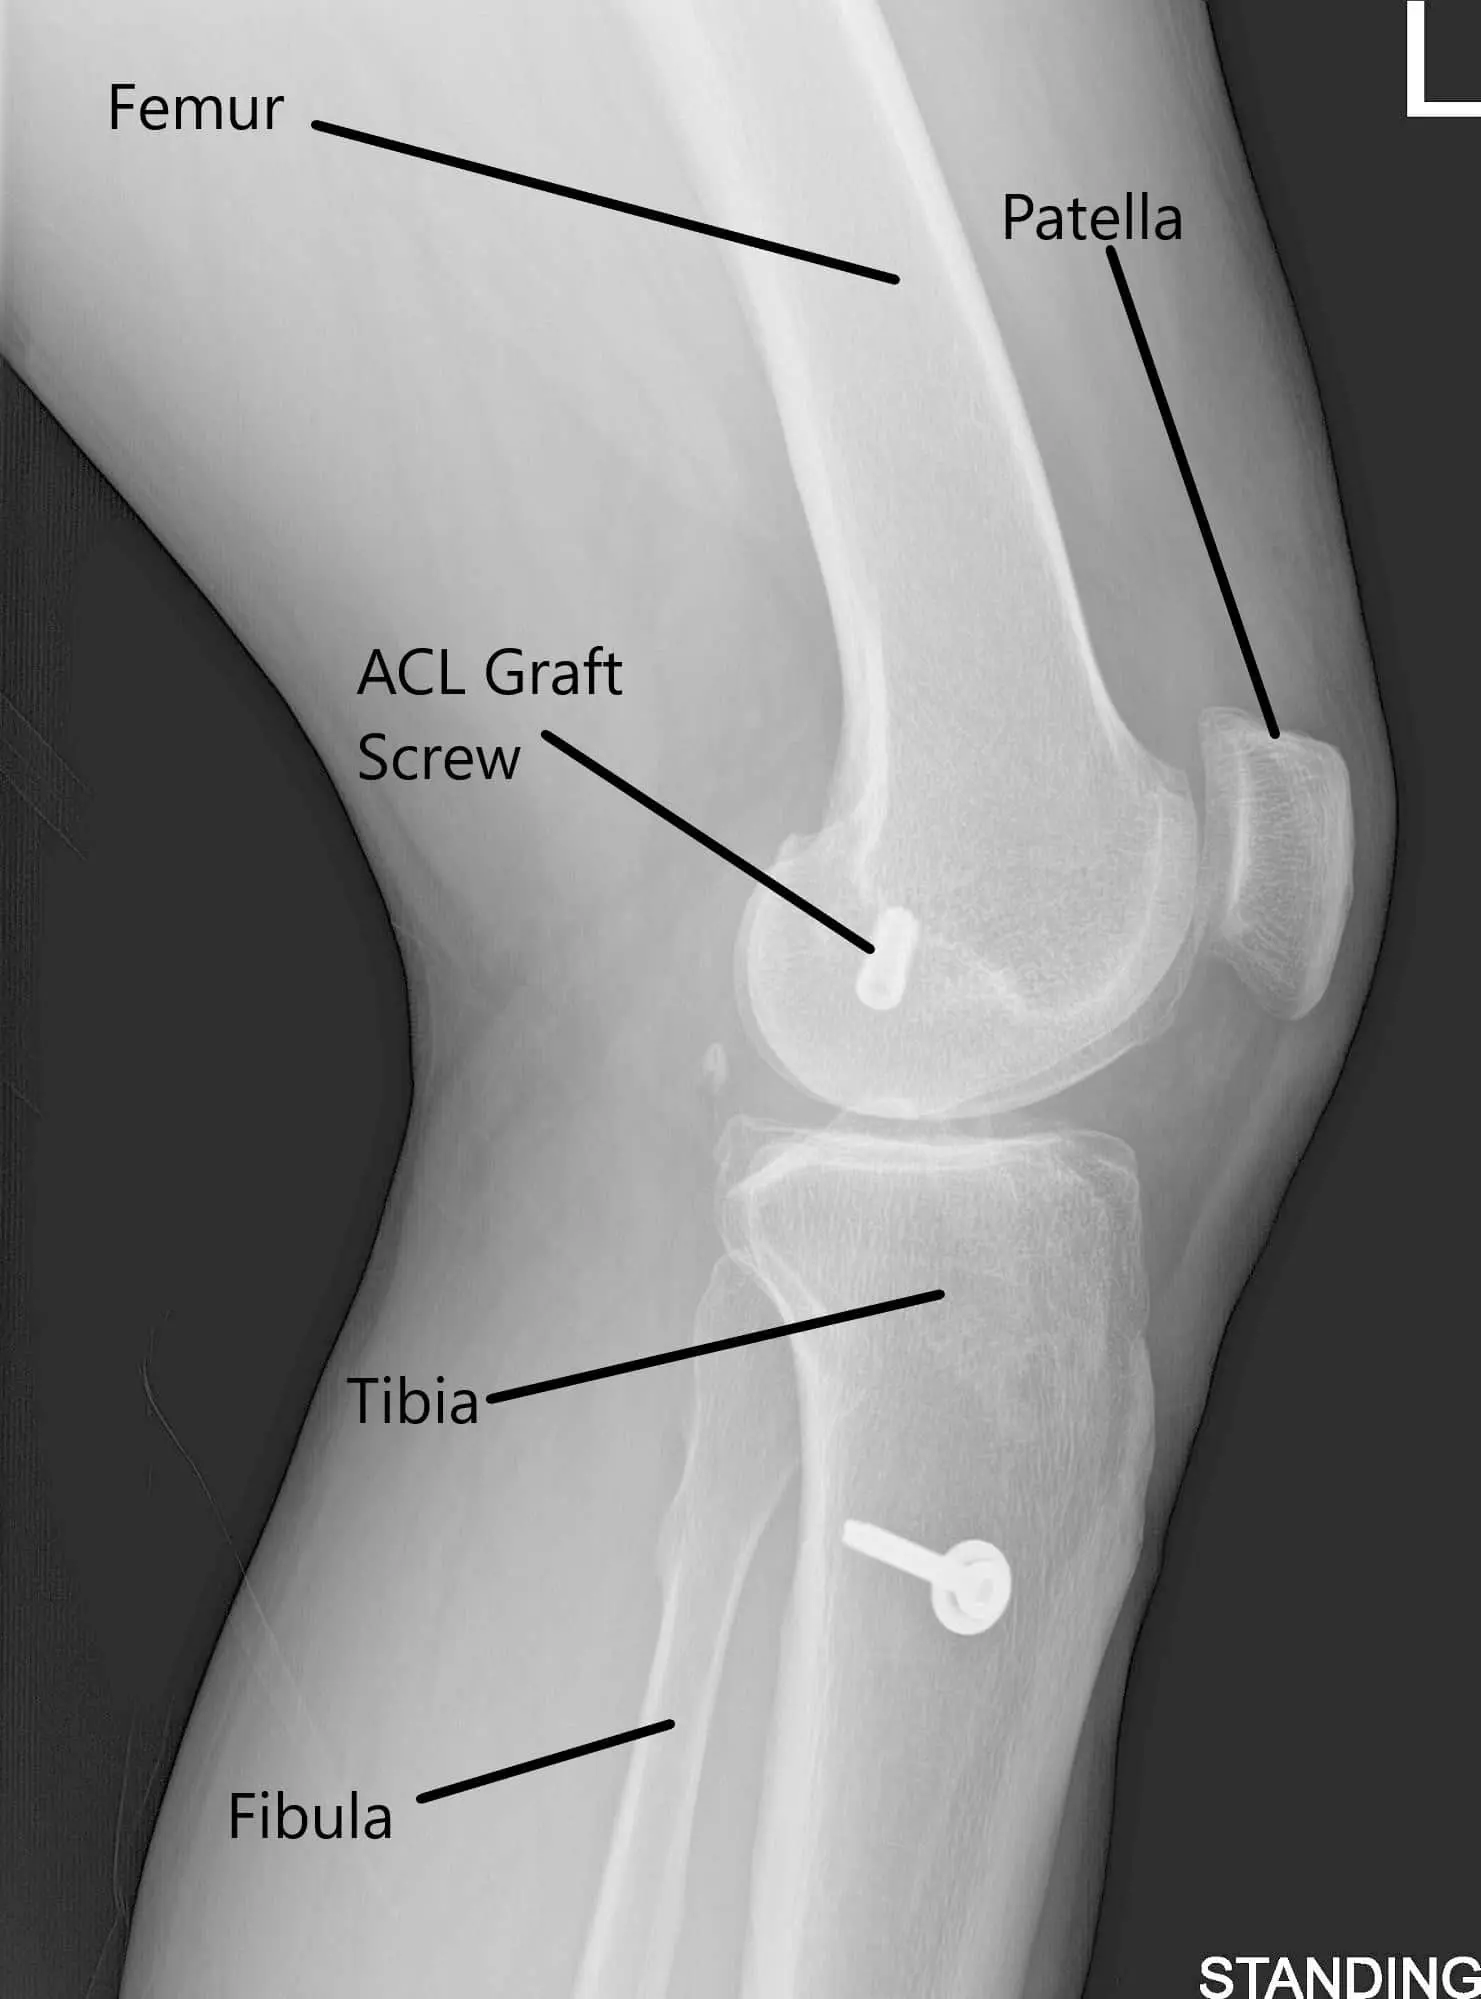

X-ray of the left knee in AP and Lateral views.

An X-ray of the left kee suggested a moderate narrowing of the medial joint compartment and status post ACL reconstruction.